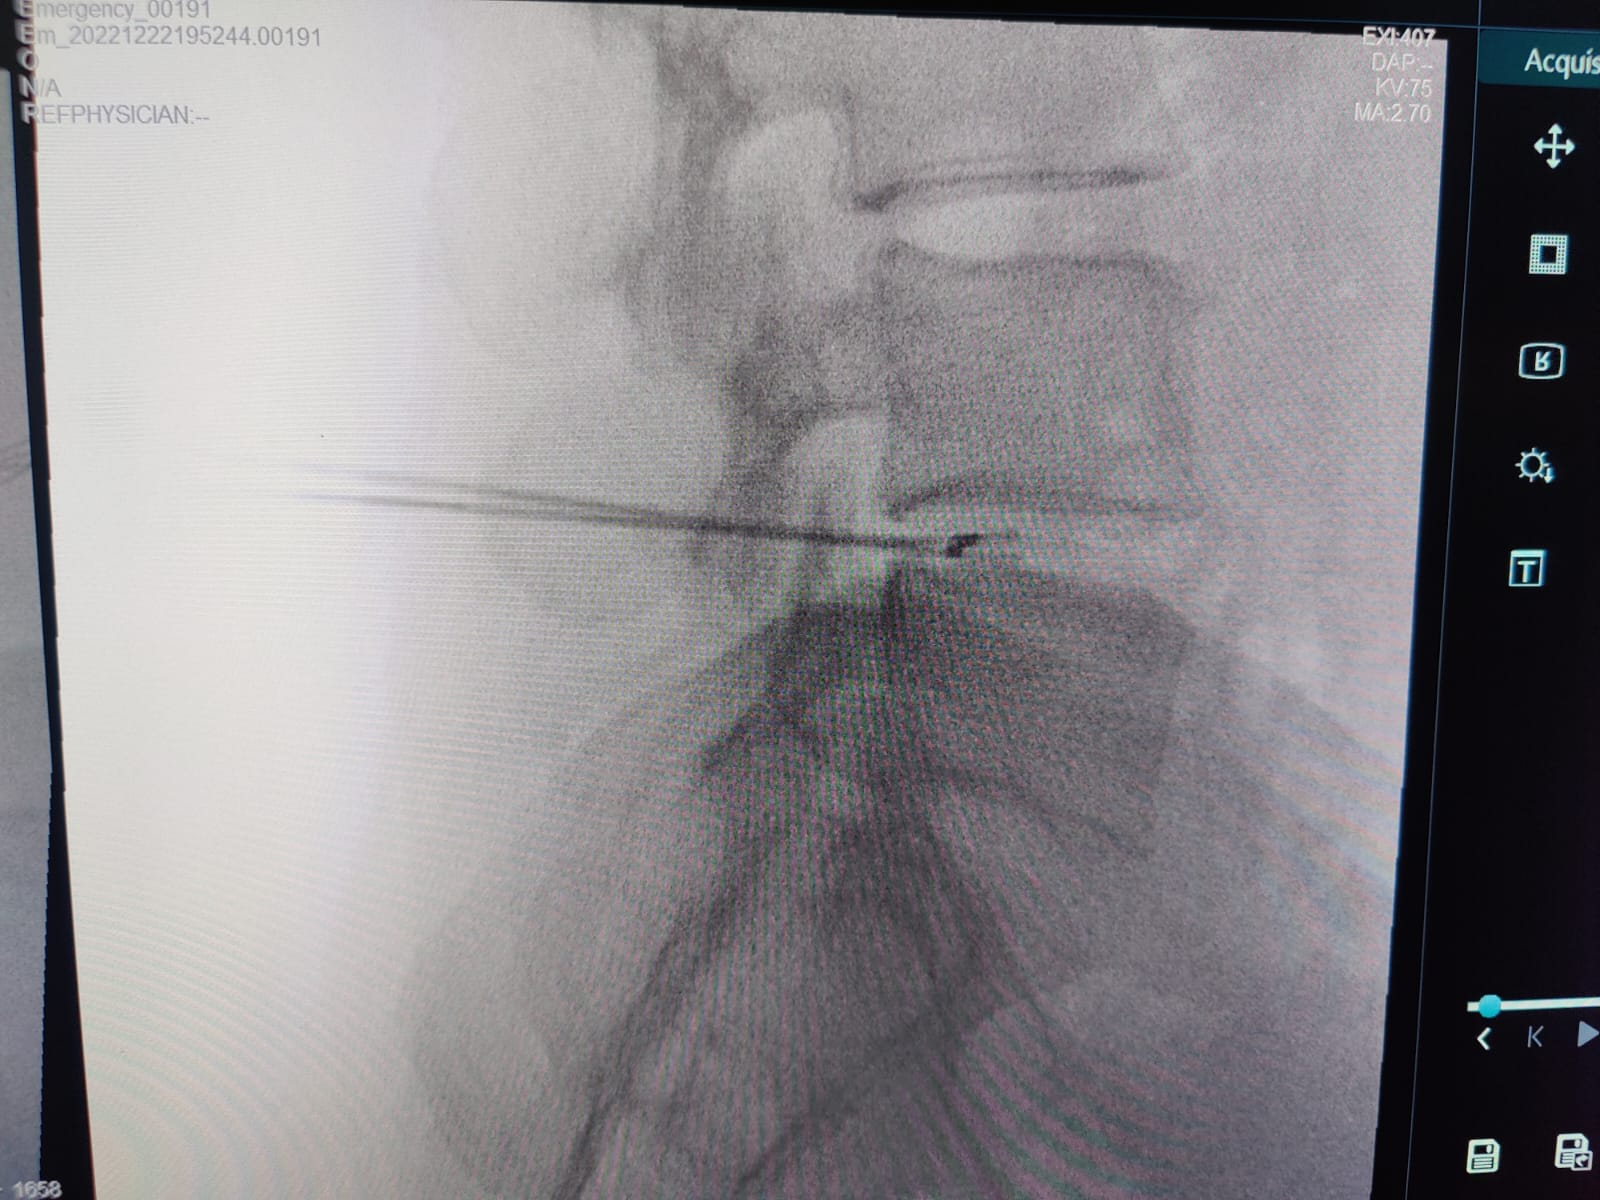

Biacuplasty involves placement of Water cooled radiofrequency needles from either side and on the posterior aspect of the Intervertebral disc. The needle tips are so placed that, at the time of lesioning there is flow of bipolar RF energy across the tips producing a zone of Ionic tissue heating. This heating in the painful area brings about the denervation of the abnormal nerves and thus, relieves the patients of the discogenic pain.